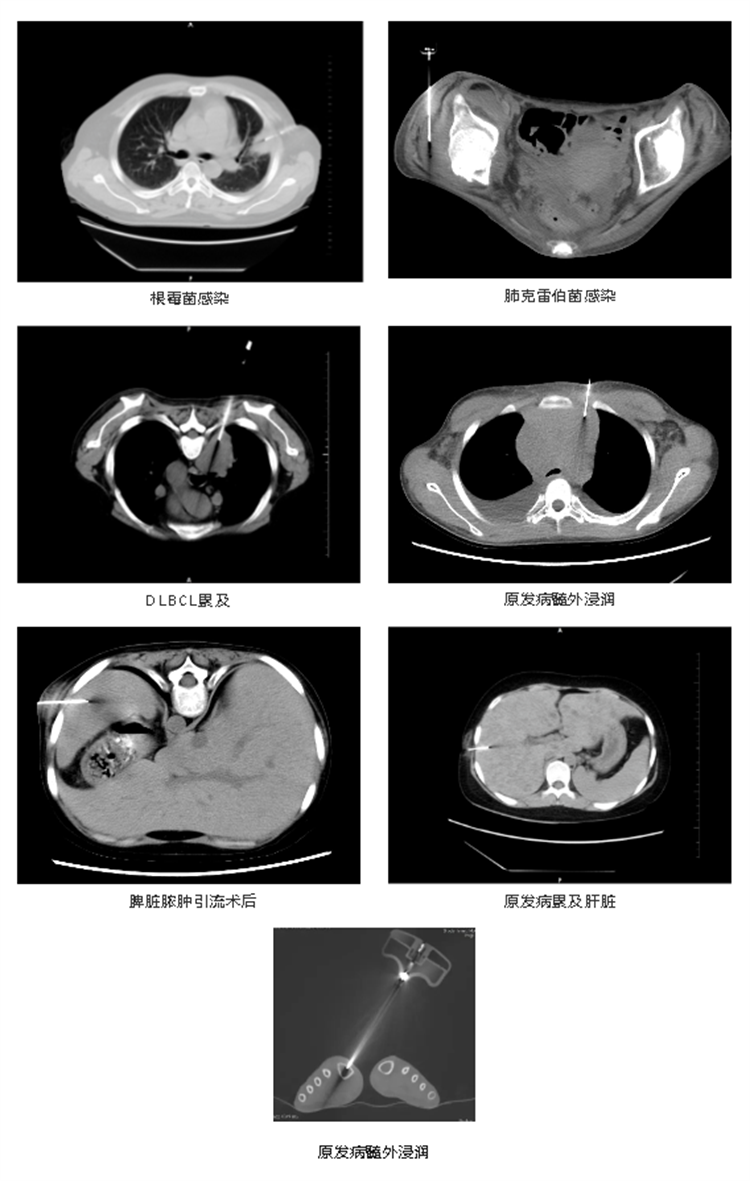

實(shí)際病例展示

657812bb507a7.png

657812c4e76c1.jpg

此項(xiàng)技術(shù)傷口創(chuàng)面小,對(duì)患者來(lái)說(shuō),經(jīng)濟(jì)適用,也可以為臨床治療和預(yù)后判斷提供更多的病理學(xué)信息和依據(jù)。